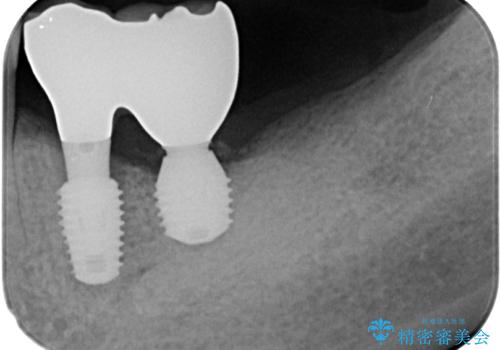

骨吸収が甚大な後方は3ヶ月ほど待機して、手前は抜歯即時埋入により、短期間インプラント補綴治療を行うこととしました。

なお、後方の歯は痛みが酷かったため、初診時に抜歯をすることとなりました。

骨吸収が大きかったため、待機期間を必要としましたが、外科処置は初診時の抜歯も含めて3回に抑えることができ、半年の短期間で治療を終えることができました。